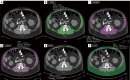

Axial CT image at the level of L3 in a 66-year-old male patient with lung and gastrointestinal cancer and a BMI of 36.9 kg/m2 (classified as obese with BMI >30 kg/m2) (A). CT-based quantification with thresholds for MA of the (B) SMA, (C) NAMA, (D) LAMA, (E) IMAT, and (F) SAT were obtained using Syngo.via software (Siemens, Erlangen, Germany). CT-based parameters indicate myosteatosis. The MA was 31 HU (myosteatosis criteria for males is <33 HU for BMI ≥25.0 kg/m2). The NAMA/TAMA index was 47% [myosteatosis criteria for males is <66.4% (T-score <2.0)]. The SAT was −94 HU and the MA/SAT index was −0.32 HU (myosteatosis criteria for males is >−0.44 HU). CT, computed tomography; BMI, body mass index; MA, muscle attenuation; SMA, skeletal muscle area; NAMA, normal attenuation muscle area; LAMA, low attenuation muscle area; IMAT, intermuscular adipose tissue; SAT, subcutaneous tissue attenuation; TAMA, total abdominal muscle area.